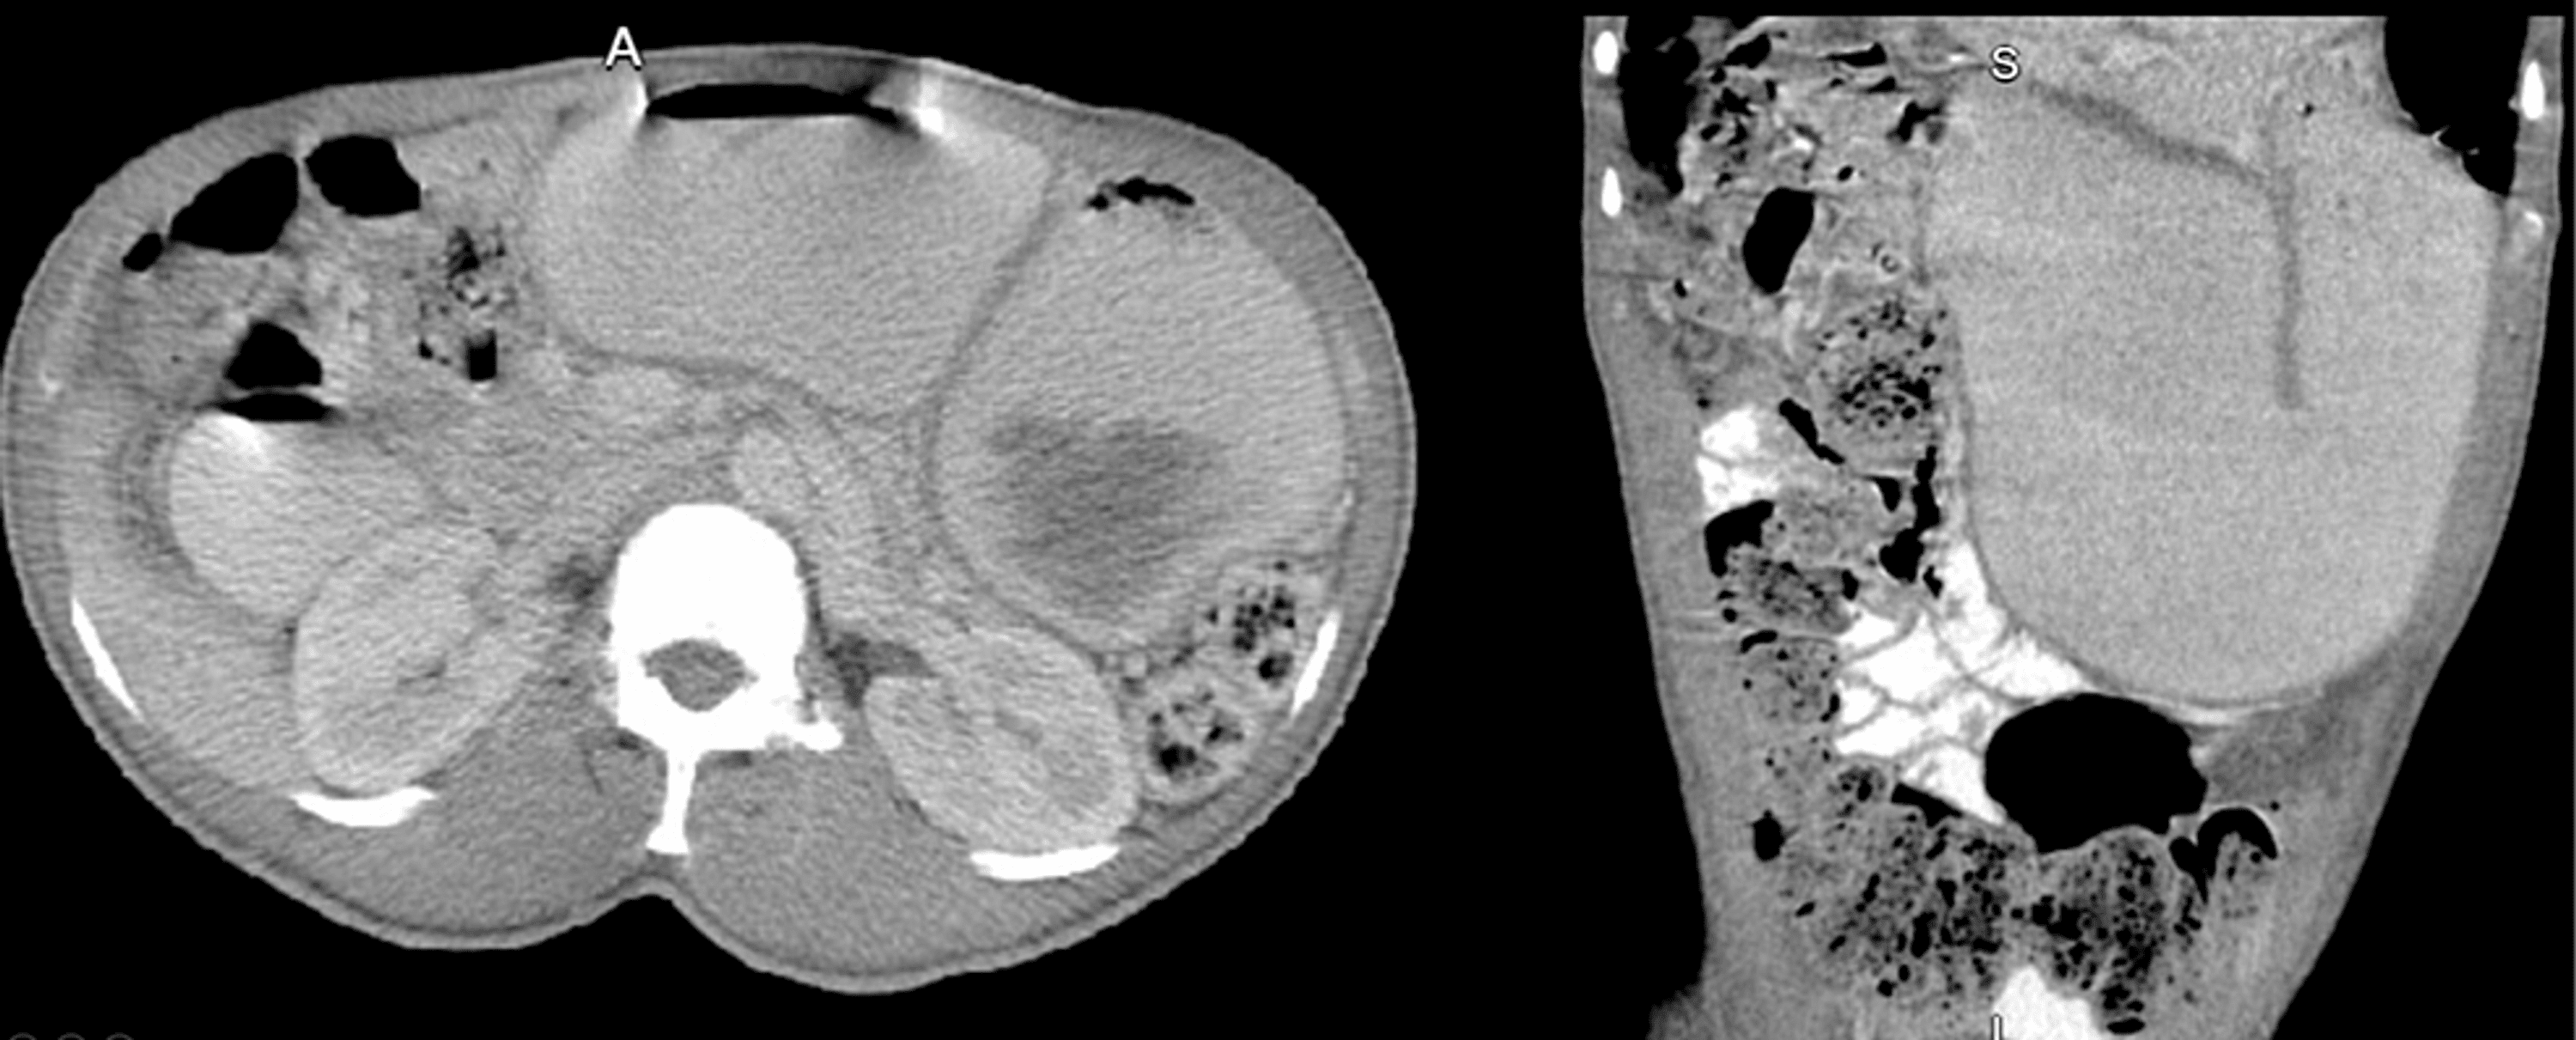

From www.reddit.com

Suspected MALS/SMAS/NCS? r/medical Pots Gastroparesis Mals Ncs The coexistence of median arcuate ligament syndrome (mals) and superior mesenteric artery syndrome (smas) is. Over one million americans are. We performed a systematic review of the literature related to pots and gastrointestinal symptoms, proposed possible mechanisms and. What is mals (median arcuate ligament syndrome)? The standard treatment is surgical release of the celiac artery by division of the median. Pots Gastroparesis Mals Ncs.